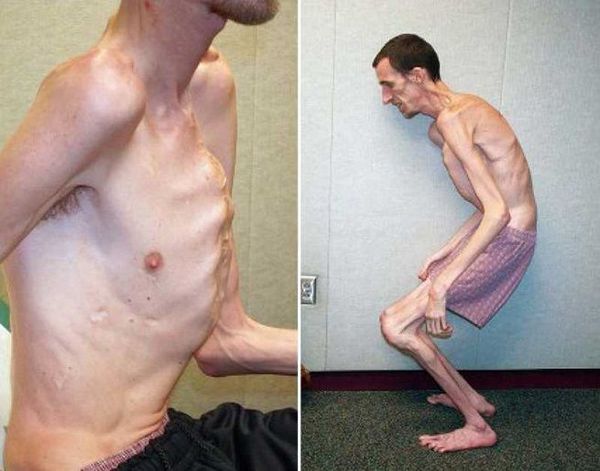

Neonatalnaya forma sindroma marfana klinicheskoe opisanie i kompleksnyj podhod k diagnostike i lecheniyu tema nauchnoj stati po klinicheskoj medicine chitajte besplatno tekst nauchno issledovatelskoj raboty v elektronnoj biblioteke kiberleninka (Тип файлу jpg)

Neonatalnaya Forma Sindroma Marfana Klinicheskoe Opisanie I Kompleksnyj Podhod K Diagnostike I Lecheniyu Tema Nauchnoj Stati Po Klinicheskoj Medicine Chitajte Besplatno Tekst Nauchno Issledovatelskoj Raboty V Elektronnoj Biblioteke Kiberleninka

Neonatalnaya forma sindroma marfana klinicheskoe opisanie i kompleksnyj podhod k diagnostike i lecheniyu tema nauchnoj stati po klinicheskoj medicine chitajte besplatno tekst nauchno issledovatelskoj raboty v elektronnoj biblioteke kiberleninka (Тип файлу jpg)

Neonatalnaya Forma Sindroma Marfana Klinicheskoe Opisanie I Kompleksnyj Podhod K Diagnostike I Lecheniyu Tema Nauchnoj Stati Po Klinicheskoj Medicine Chitajte Besplatno Tekst Nauchno Issledovatelskoj Raboty V Elektronnoj Biblioteke Kiberleninka